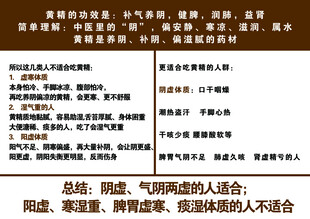

黄精 共享分:40

黄精 共享分:40 -

黄精的功效 共享分:40

黄精的功效 共享分:40 -